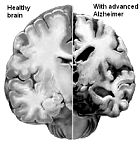

Nu zijn er volgens de World Alzheimer Reports [alz.co.uk] ongeveer 40 miljoen mensen met Alzheimer op deze planeet, maar dat aantal verdubbelt elke 20 jaar. Alzheimer wordt een epidemie. Of die jou gaat treffen, heb je gedeeltelijk zelf in de hand. Volgens epidemiologen van het Amerikaanse Taub Institute zijn er twee leefstijlfactoren die gezamenlijk je kans op Alzheimer halveren.

De Alzheimer-epidemie